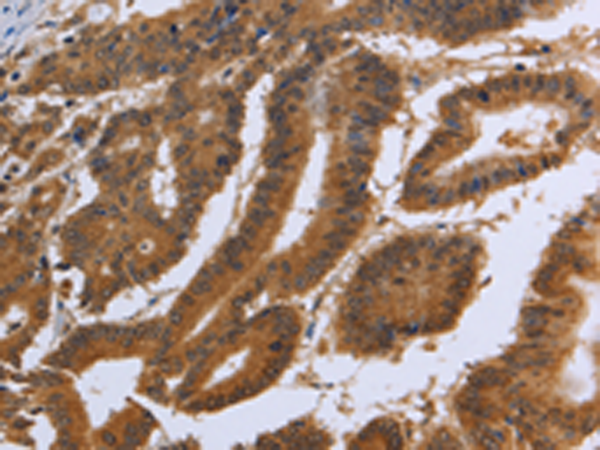

分类: 科研抗体货号: P10851别名: EVEC; UP50; ADCL2; ARMD3; DANCE; ARCL1A; FIBL-5; HNARMD应用: IHC反应种属: Human, Mouse, Rat